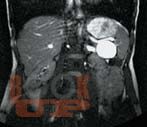

В руководстве приведен анализ и систематизирован опыт Института хирургии им. А.В. Вишневского и зарубежных авторов по вопросам диагностики и хирургического лечения кистозных опухолей поджелудочной железы. Описаны клинические проявления и анамнестические данные, характерные для таких пациентов. Дана ультразвуковая, компьютерно-томографическая, магнитно-резонансно-томографическая и эндоультразвуковая семиотика кистозных опухолей. Показаны возможности пункционной диагностики с исследованием цитологического состава кистозных опухолей и определением уровня онкомаркеров в их содержимом.